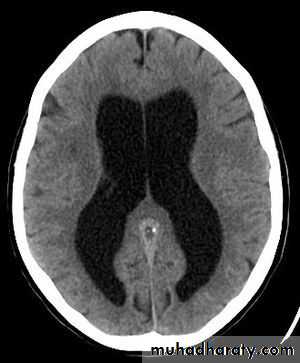

Hydrocephalus

Hydrocephalus is not a specific disease; that result from impaired circulation and absorption of CSF .

Hydrocephalus resulting from obstruction within the ventricular system is called obstructive or non communicating hydrocephalus.

Hydrocephalus resulting from obliteration of the subarachnoid cisterns or malfunction of the arachnoid villi is called nonobstructive or communicating hydrocephalus.

Clinical manifestations

It is variable and depends on many factors, including the age at onset, the nature of the lesion causing obstruction, duration and rate of increase intracranial pressure (ICP).In infants:

Accelerated rate of enlargement of the head .

The anterior fontanel is wide open and bulging, and the scalp veins are dilated.

The forehead is broad, and the eyes deviate downward, producing the setting-sun sign.

Long-tract signs including brisk tendon reflexes, spasticity, and + ve Babinski sign.

In older child

The cranial sutures are partially closed so that the signs of hydrocephalus become difficult.Headache is a prominent symptom in older patients.

Irritability, lethargy, poor appetite,and vomiting are common .

A gradual change in personality and a deterioration in academic productivity

Examination:

1-Serial measurements ofthe head circumference(OFC)

3-Fundoscopy (Papilledema), abducens nerve palsy, and pyramidal signs mainly in the lower extremities

• 2-Percussion of the skull may

• produce a cracked pot sound,

• indicating separation of the sutures.